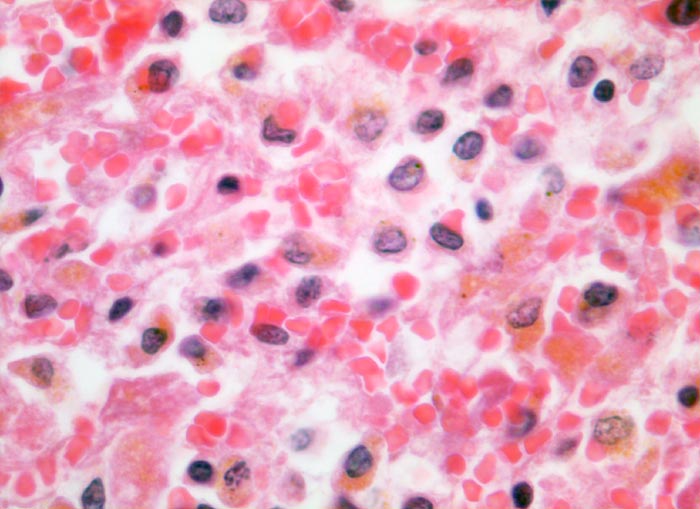

Linksherzversagen oder ein Schockzustand können zu einer hepatischen Minderperfusion mit ischämischen Koagulationsnekrosen der perivenulären Hepatozyten führen. Die Kombination von Hypoperfusion und retrograder Stauung (Rechtsherzversagen) führt zu zentrilobulären hämorrhagischen Nekrosen. Klinisch führen diese Nekrosen zu einer transienten geringen bis mässigen Erhöhung der Transaminasewerte, gelegentlich auch zu einem leichten Ikterus.

Metastasierendes Kolonkarzinom. Als Todesursache fanden sich nicht ganz frische zentrale und perizentrale Lungenembolien.